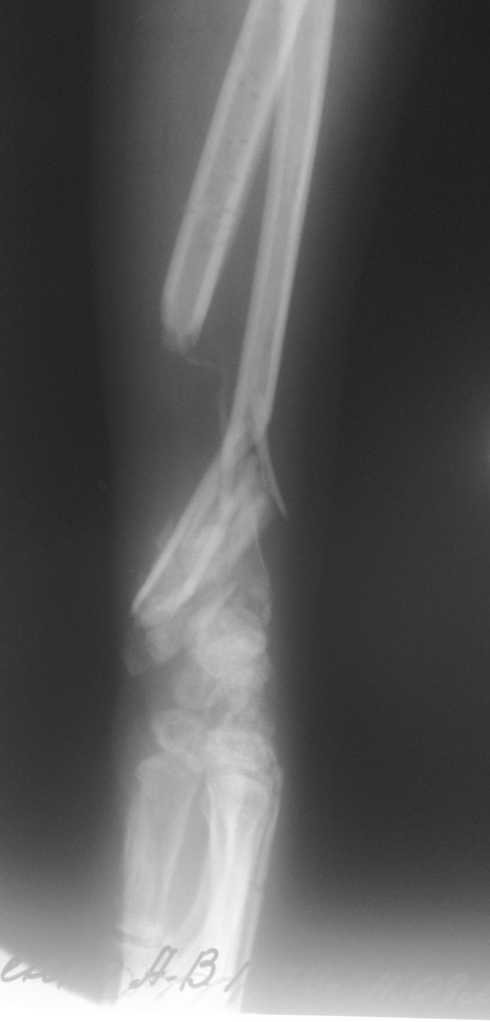

Имеется постттравматический дефект дистальных отделов костей левого предплечья.

Больная Д. 30 лет плучила травму 12.07.09г, пассажир скутера - тяжелая сочетанная травма брюшной полости и конечностей, гемоперитониум, закрытый перелом н\3 ЛЕВОГО БЕДРА, открытый перелом н/3 левого предплечья с дефектом обеих костей, рана голени. С момента травмы перелом предплечья был фиксирован анкерно-спицевым апаратом, проводилось лечение других сегментов. В настоящий момент АВФ демонтирован, имеется следующая рентгенологическая картина (см. приложение), имеется дефект обеих костей и суставных поверхностей. Коллеги подскажите варианты лечения в данном случае ?!

Уважаемый коллега! В данном случае остается одно - формирование артродеза лучезапястного сустава в положении полусупинации (функциональном для левой руки)и восстановление лучевой кости. Труднее это выполнить. На мой взгляд, если нет концевого остеомиелита и трофических язв конечности, можно произвести остеосинтез пластиной с угловой стабильностью лучевой кости с пластикой дефекта аутокостью из подвздошной кости и из дистального фрагмента, если будет необходима резекция выступающего в ладонную сторону отломка. Лучше, если удасться адаптировать положение кисти (устранить тыльное смещение) с минимальной резекцией, освежив поверхности костей запястья и дисальный конец дистального отломка луча. Если есть инфекция - билокальный остеосинтез луча по Илизарову.